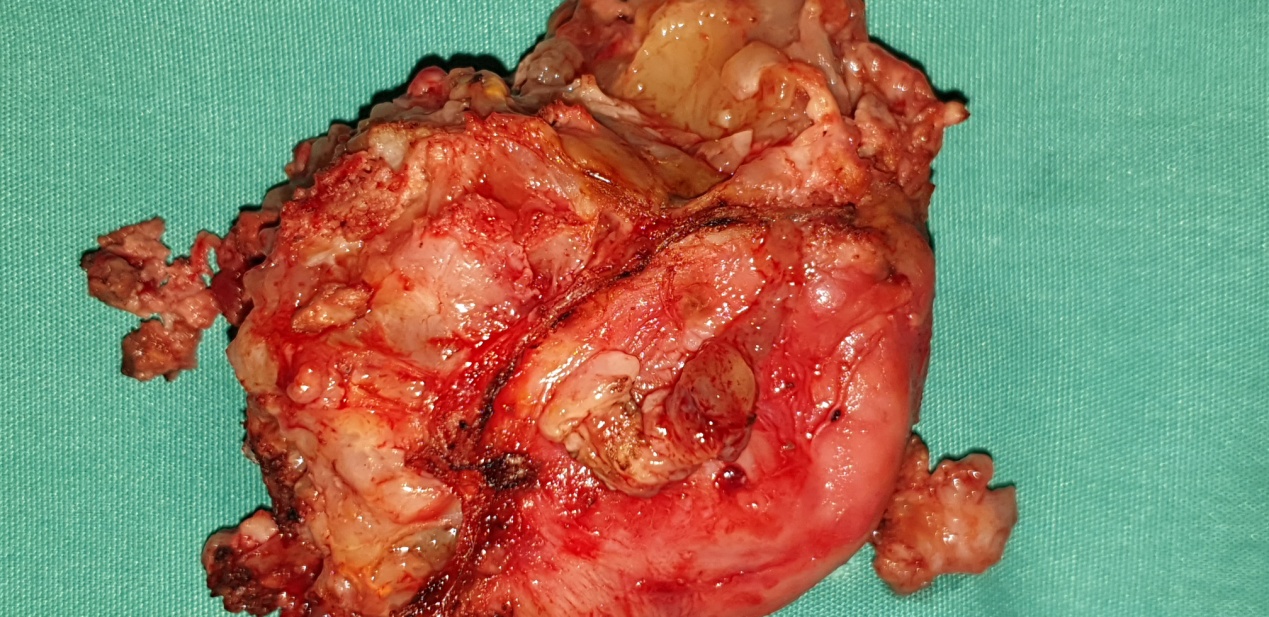

Surgical specimen. Complete resection of the tumor together with a segment of rectum (Courtesy Dr. V. Penopoulos)